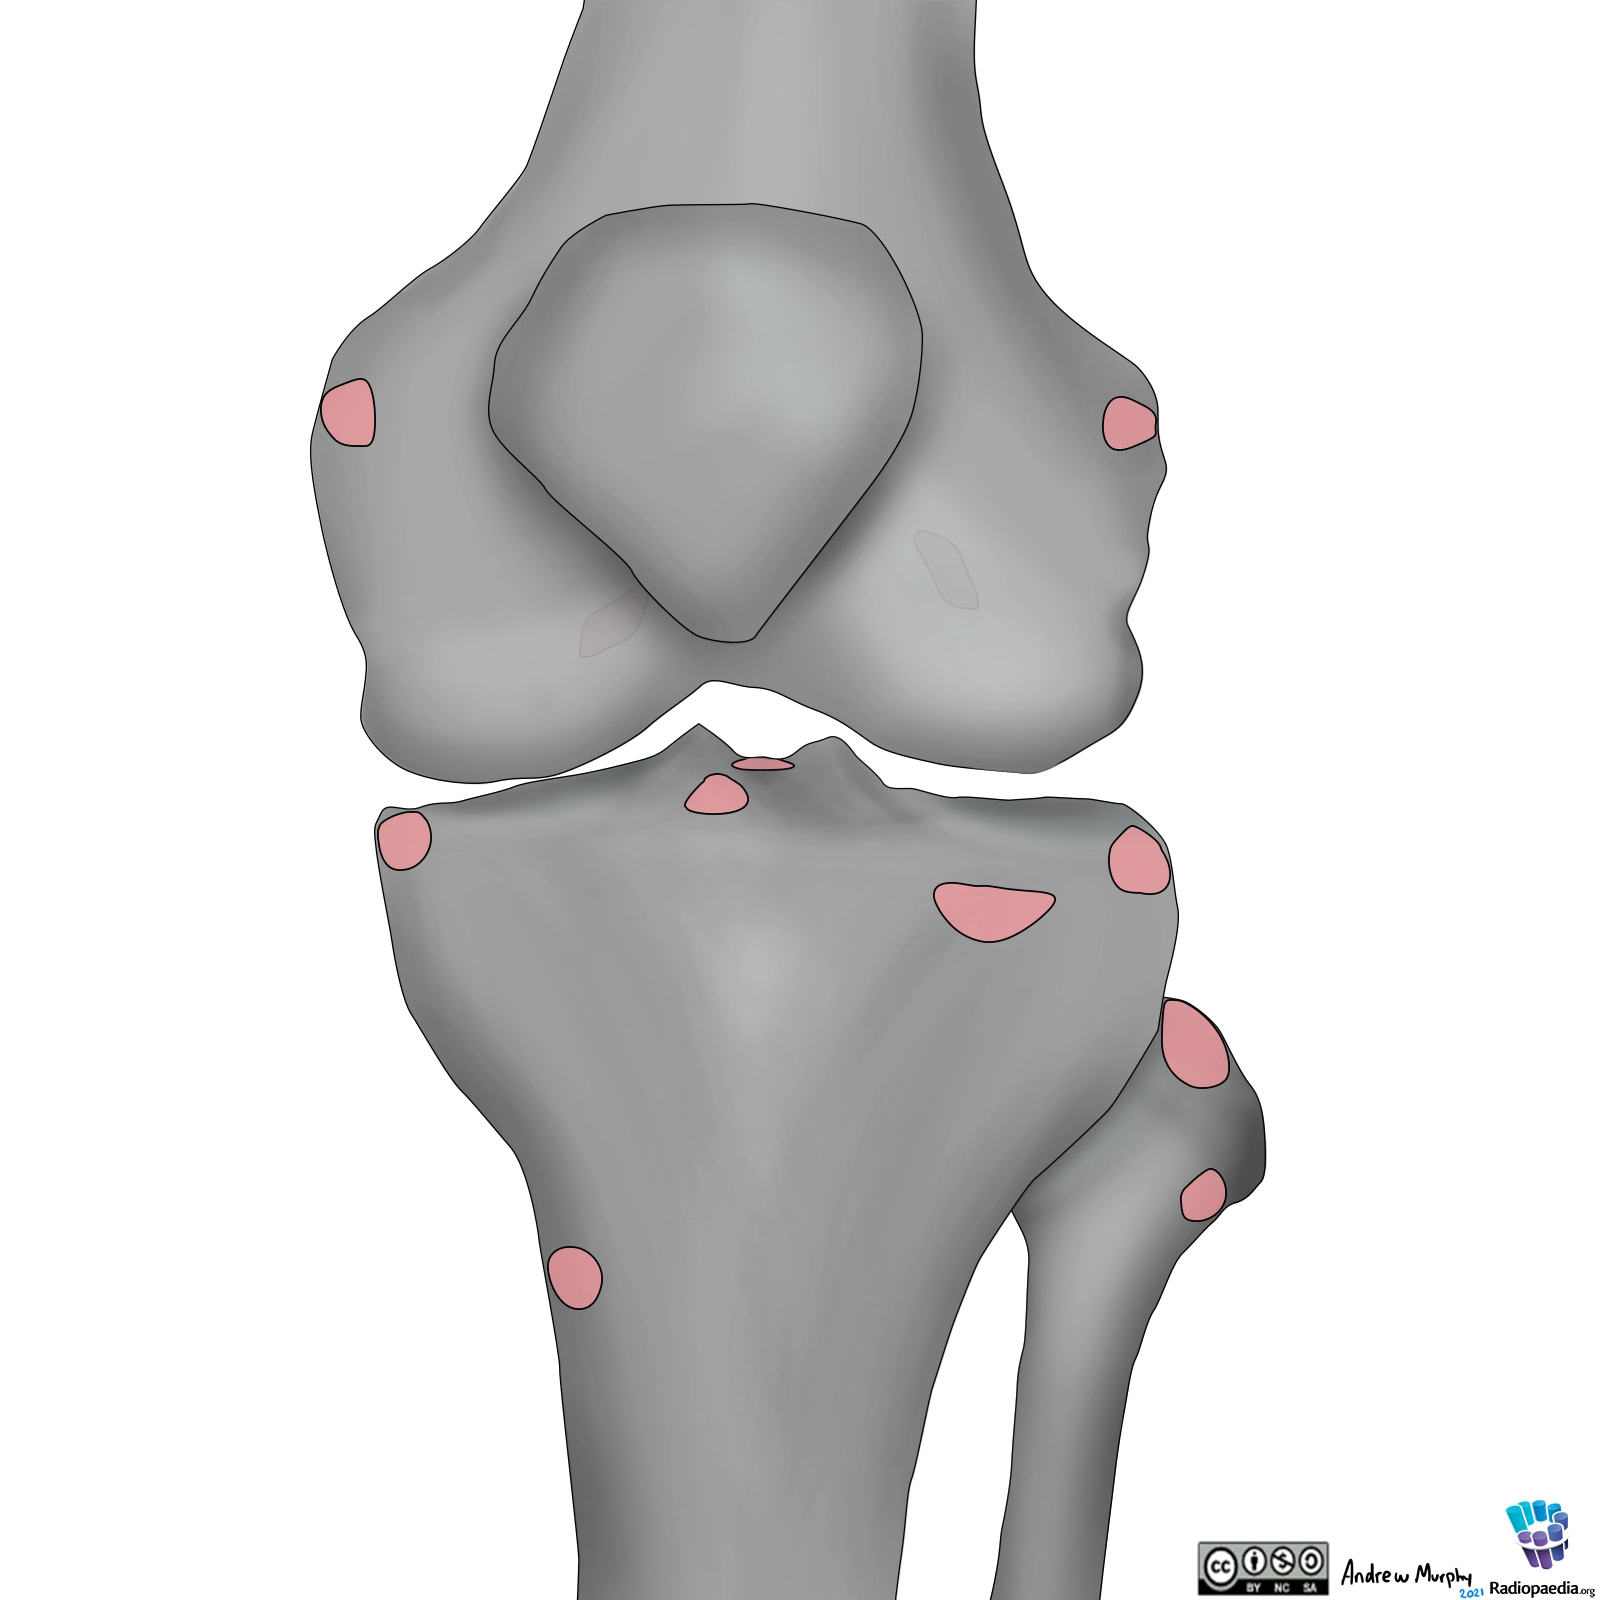

X quang khớp gối